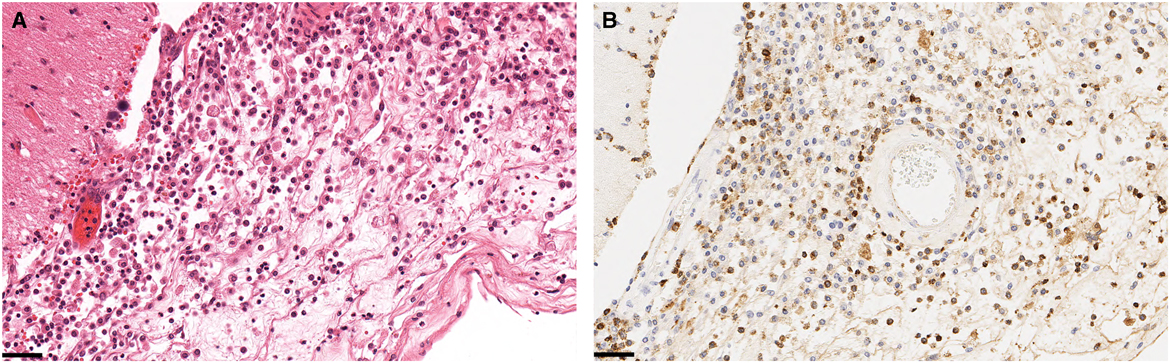

An autopsy was performed. Her bone marrow was hypercellular with myeloid hyperplasia and increased monocytes consistent with chronic myelomonocytic leukemia (CMML). Her World Health Organization subtype of CMML was CMML-0.Reference Arber, Orazi and Hasserjian 4 Her International Prognostic Staging System CMML score was 1.0, Intermediate-1 category. Her myelofibrosis (MF) grading was MF2 (out of 3). Monocytic cells, neutrophils, and early myeloid cells had also infiltrated her periorbital soft tissue, retinas, sclerae, and leptomeninges (Figure 2). All cultures and special stains of sampled tissue were negative for fungal elements.

Figure 2 Histologic specimens taken at autopsy of the periorbital soft tissues and leptomeninges. Hematoxylin and eosin staining (A) shows monocytic cells, histiocytes, and neutrophils. Adjacent tissues with myeloperoxidase stain (B) reveal myeloid cells, consistent with infiltration by chronic myelomonocytic leukemia. The black scale bars are 50 μm. No fungal elements are seen with Grocott’s methenamine silver stain or periodic acid–Schiff–diastase special stains (not shown).